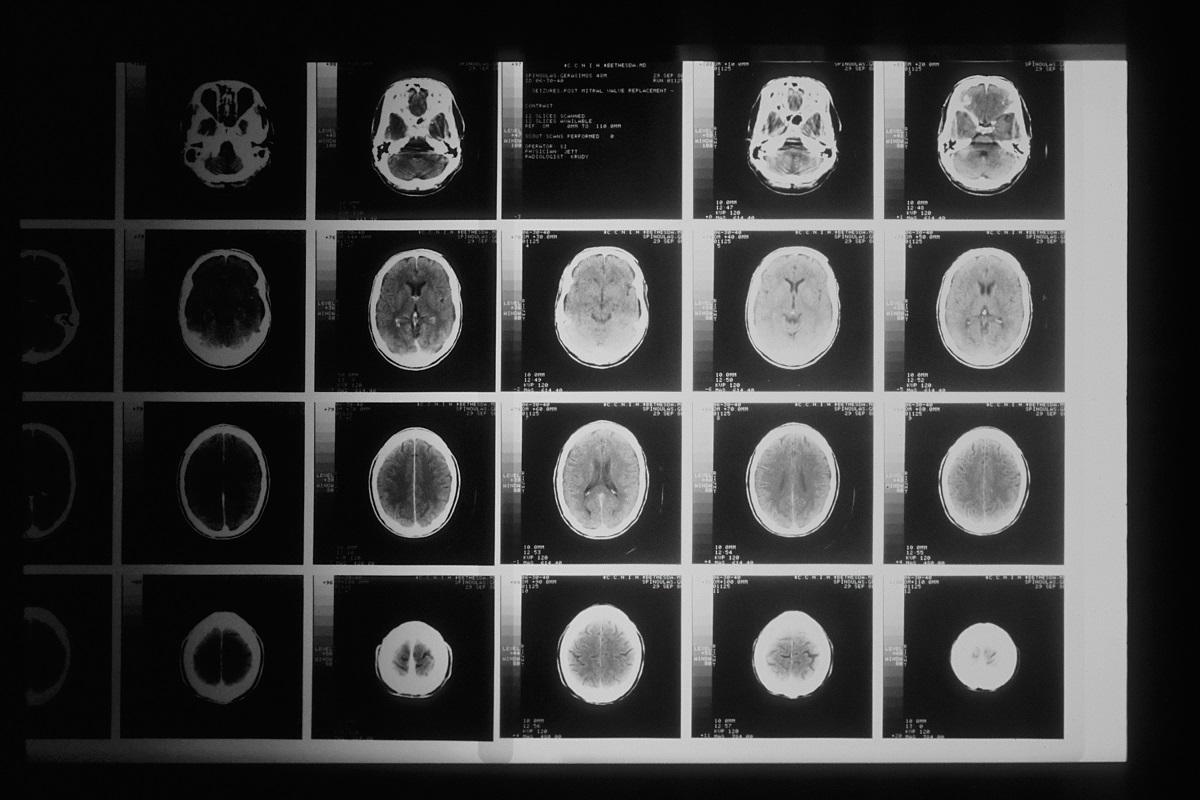

Le glioblastome fait partie des formes de cancer du cerveau les plus agressives et compte pour 12 à 15 % des cas de tumeurs intracrâniennes chez les adultes. Malgré les percées majeures dans la recherche sur le cancer, le glioblastome continue de résister à la radiothérapie et à la chimiothérapie.